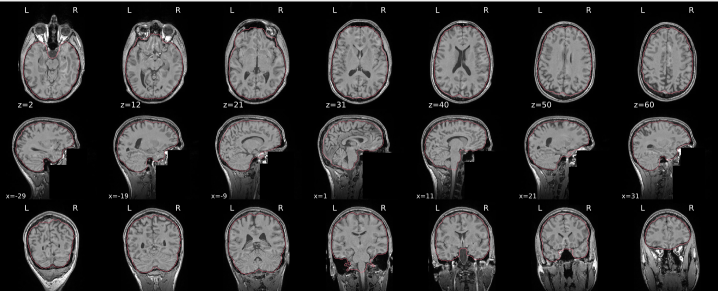

T1w skull stripping

Skull stripping is the process separating the brain (cortex and cerebellum) from the skull. The red line follows the outline of the brain and it separates it from the skull.

Example of a good subject

- There are no skull stripping errors, such as portions of the brain missing, or too much of the skull retained

- The red line follows the outline of the brain

Example of a bad subject

- There are skull stripping errors, such as portions of the brain missing, or too much of the skull retained

- NOTE: check all the images (slices) in the report. If only one image (slice) looks problematic, it is possible that the subject is okay and it is just a visual issue in that particular screenshot

Summary

| Good | Bad |

|---|---|

| The brain is fully inside the red line | Structures like the cranium or the eyes are inside the red line |

| No important brain structures are outside of the red line red line follows the natural outline of the brain | Important brain structures are missing inside of the red line |

-> if only one slice is problematic, it could be an issue related to the visual depiction of the data instead of an issue related to the test subject